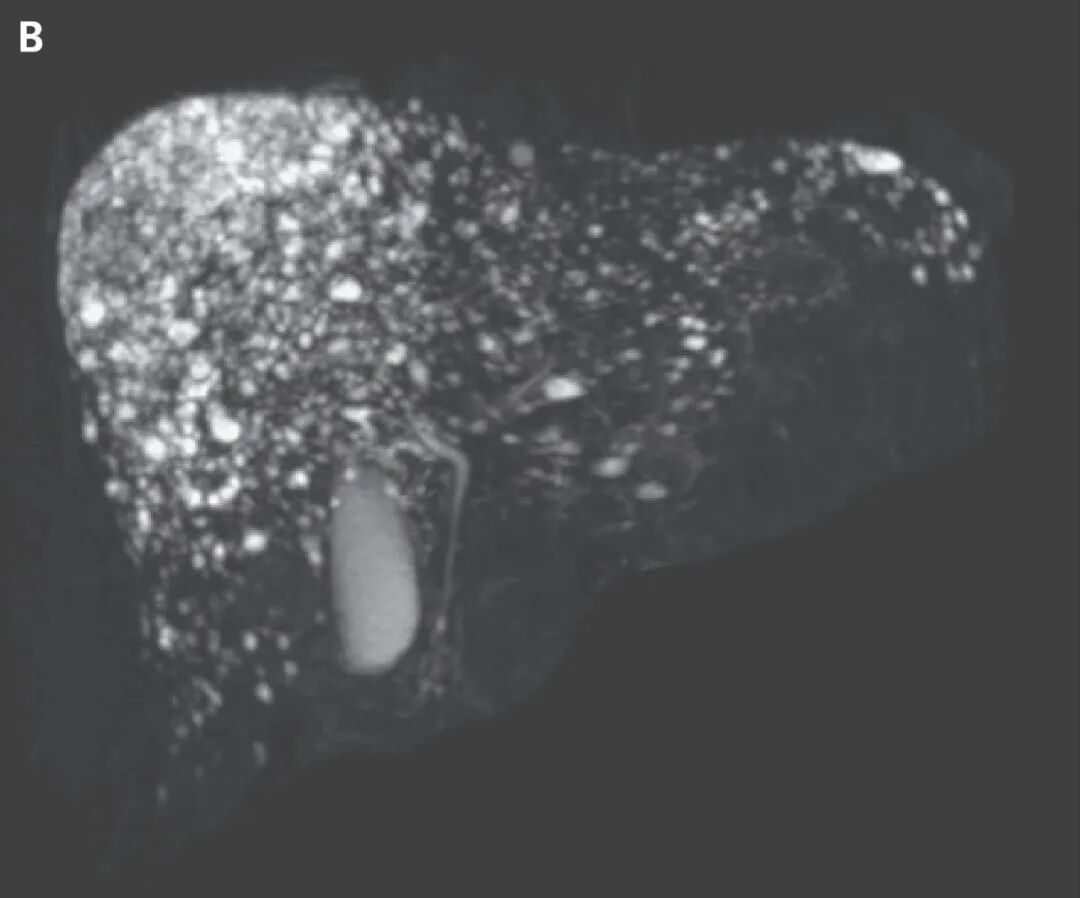

MRI与胰胆管造影显示肝内多发T2加权高信号囊性小结节,与胆管无交通,呈“星空征”(图B)。